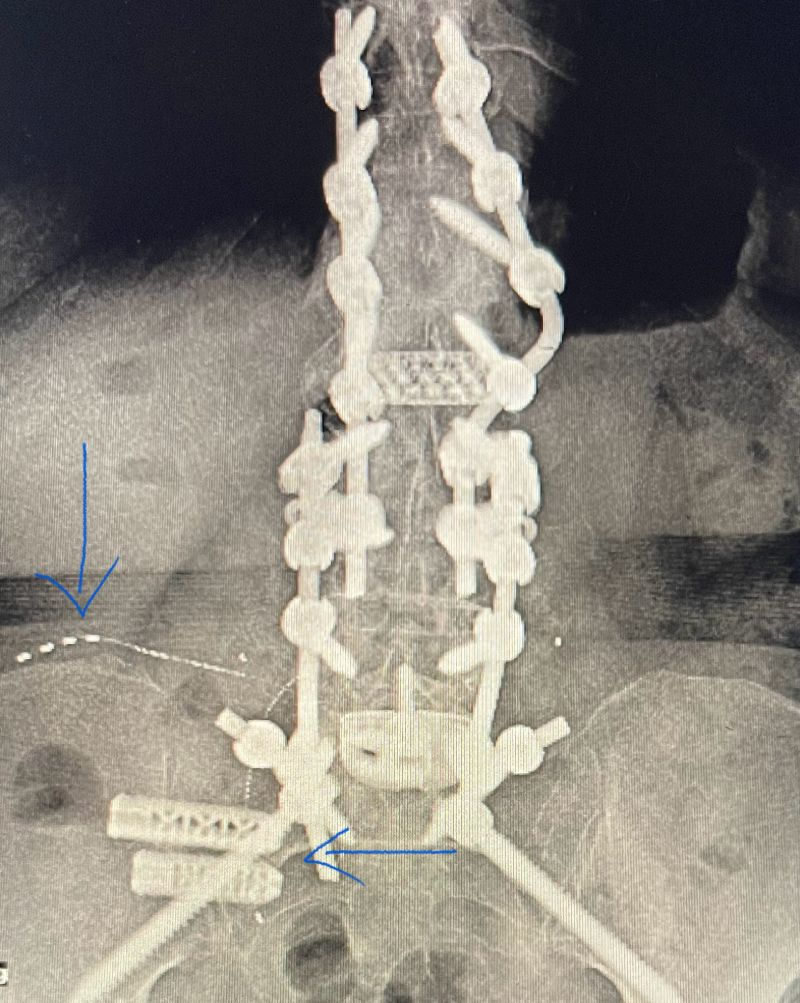

1717509490778.png

Now pain free, on no meds, and runs 5K regularly.

How would one help out the patient in image there?

Just to counter argue here.

Opiates no research

Cluneal nerve stimulation no research

I’m sure adjuncts have been tried and failed

Meditation, acceptance and PT tried but patient miserable

The pts in the image above will suck your soul from your body and you'll never make any money in the process. I realize how that sounds, but it is unfortunately the reality of medicine today IMO. If you're in private practice (I am), you can't see people like the one above unless you're offering opiates and that's all you're doing.